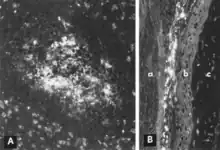

Acute infection of postnatal pigs, including pregnant dams that subsequently develop reproductive failure, is usually subclinical.[11][12][13][14][15][16] However, in young pigs and probably in older breeding stock as well, the virus replicates extensively and is found in many tissues and organs with a high mitotic index. Viral antigen is especially concentrated in lymphoid tissues[13][14] (Fig. 3A, B). Many pigs, irrespective of age or sex, have a transient, usually mild, leukopenia sometime within 10 days after initial exposure to the virus.[11][17][15][16] PPV and other structurally similar viruses have been identified in the feces of pigs with diarrhea.[18][19] However, there is no experimental evidence to suggest that PPV either replicates extensively in the intestinal crypt epithelium or causes enteric disease as do parvoviruses of several other species.[13][20] PPV also has been isolated from pigs with lesions described as vesiclelike. The causal role of PPV in such lesions has not been clearly defined.[21]

Replication of PPV in vitro is cytocidal and characterized by "rounding up," pyknosis, and lysis of cells (Fig. 1A). Many of the cell fragments often remain attached, eventually giving the affected culture a ragged appearance. Intranuclear inclusions develop[31] but they are often sparsely distributed.[39] Infected cultures may hemadsorb slightly[31] (Fig. 1B). Cytopathic changes are extensive when cell culture-adapted virus is propagated under appropriate conditions. However, on initial isolation several serial passages of the virus[31] or, better, the infected culture may be necessary before the effects are recognized. The use of immunofluorescence (IF) microscopy greatly increases the likelihood of detecting minimally infected cultures.[40][41]